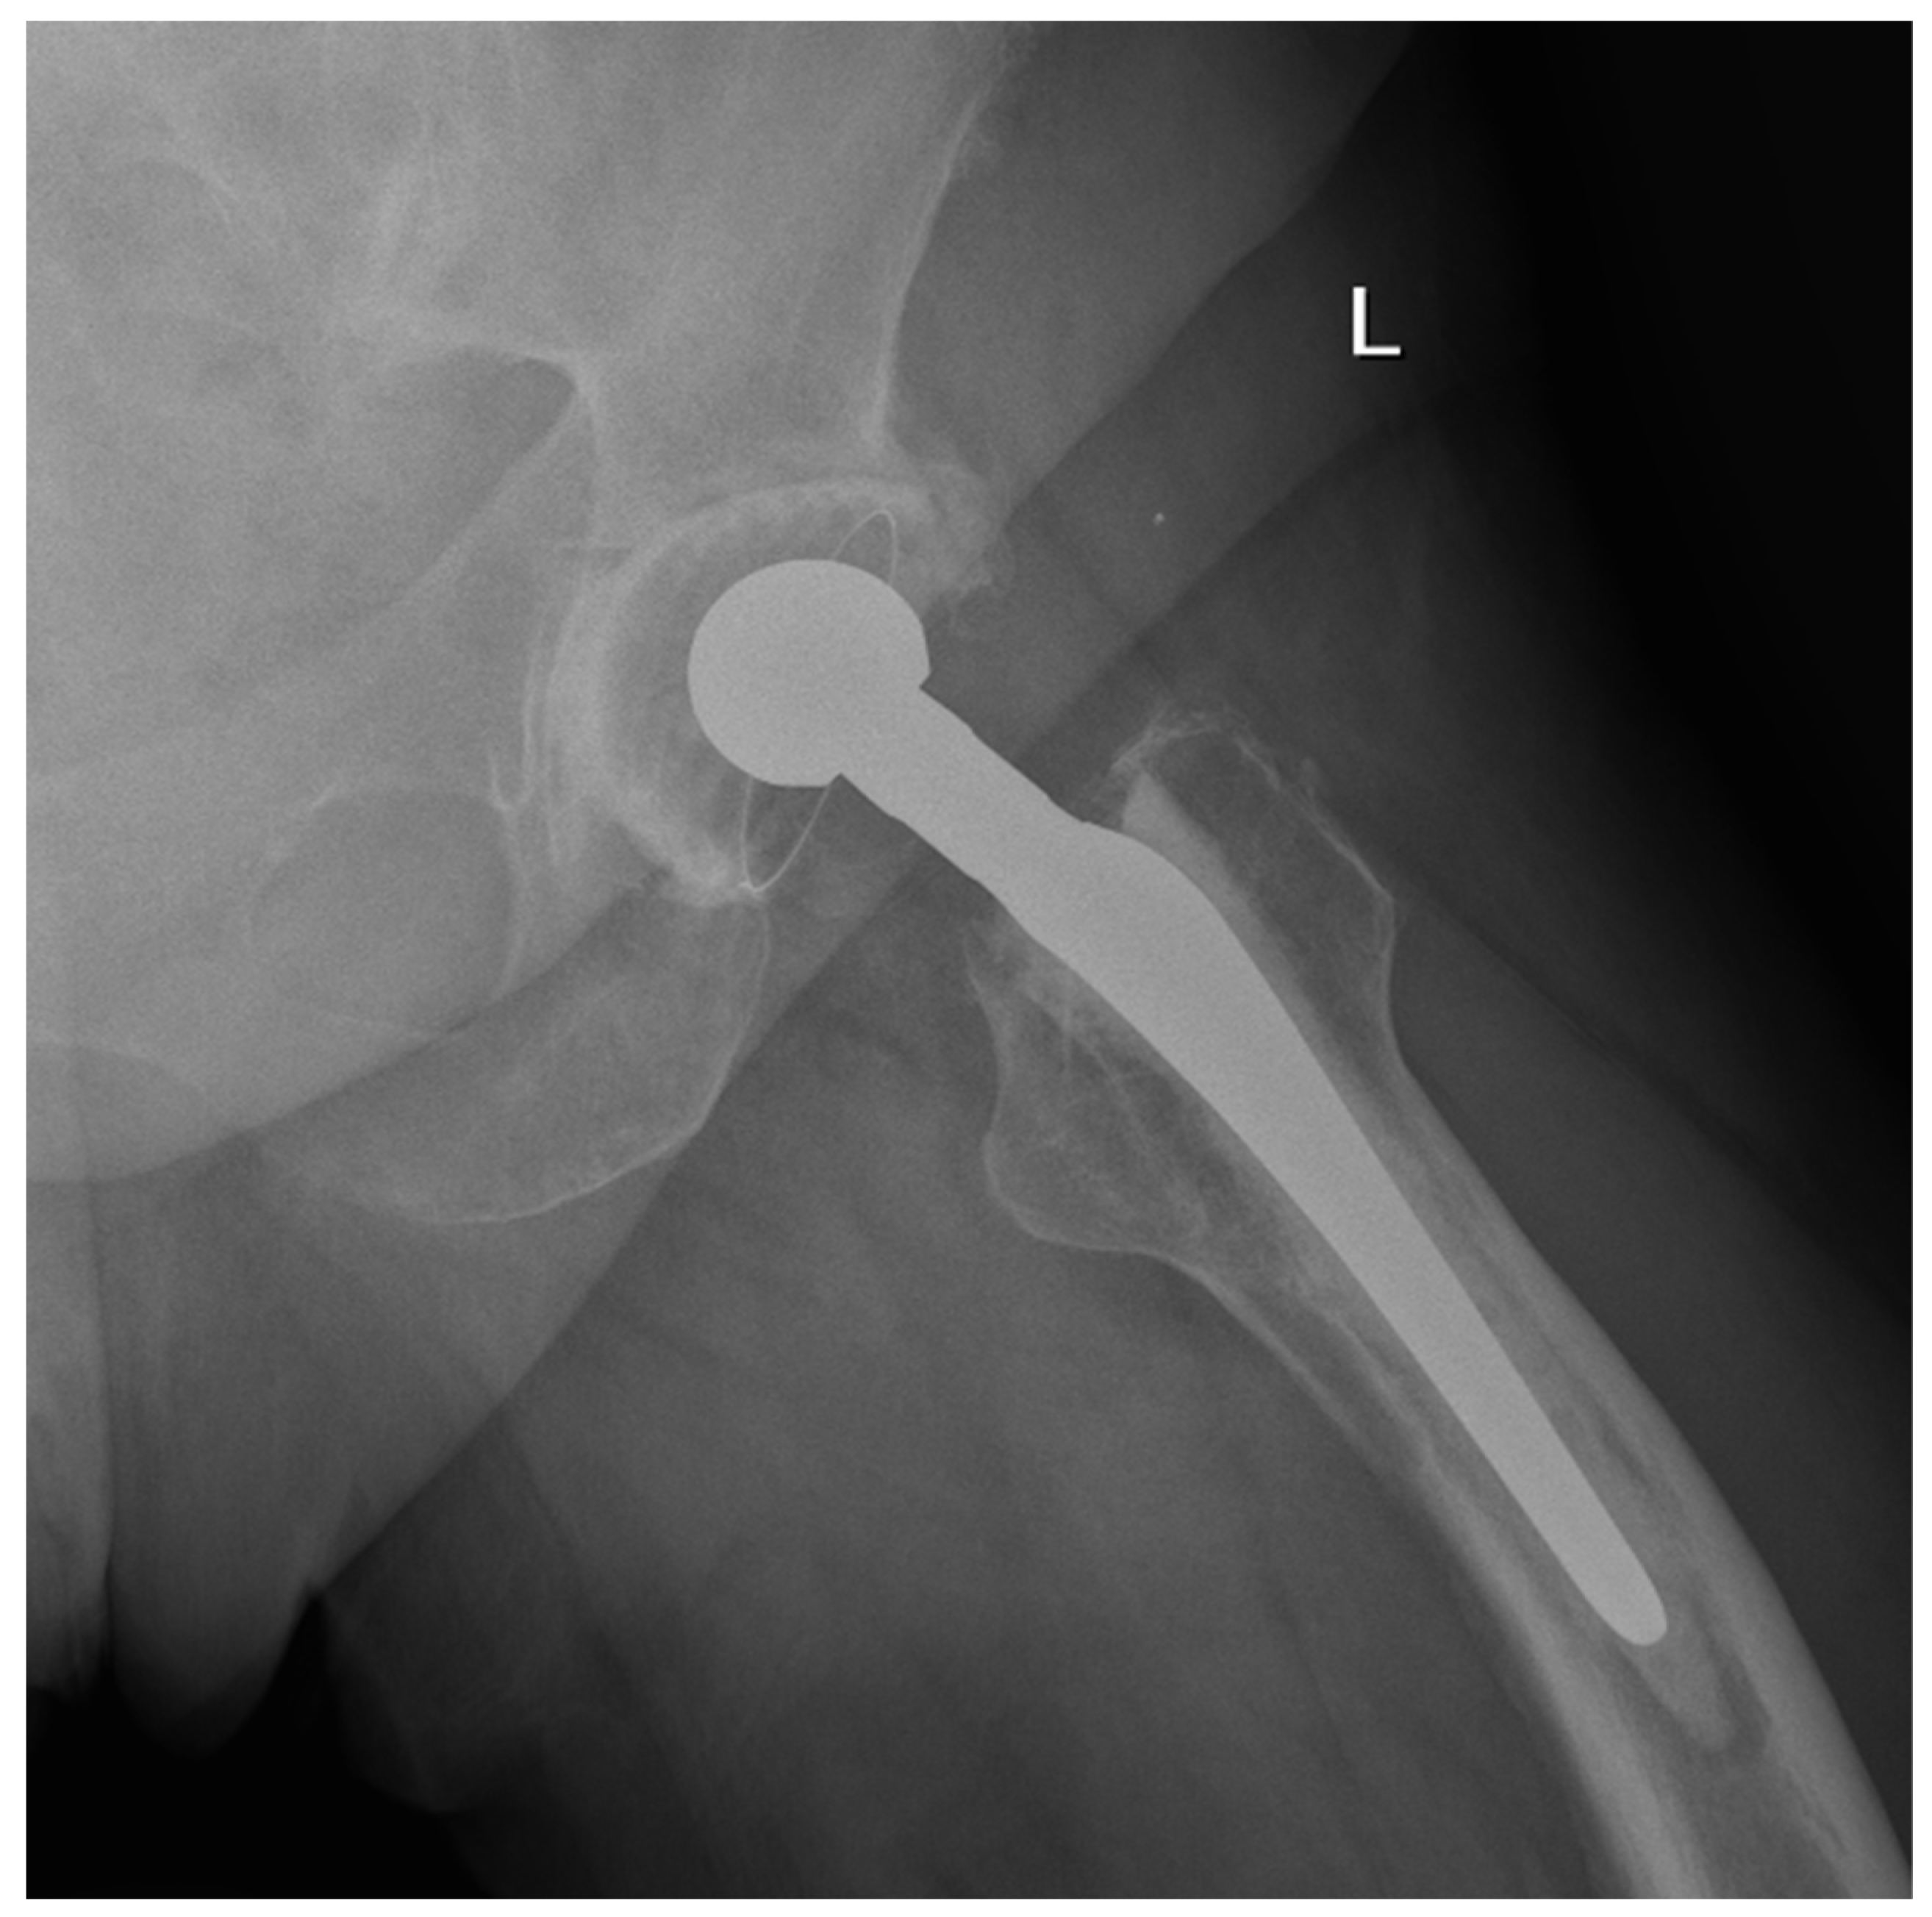

We observed a positive correlation between the increase in the mean oxidation index (OI) of the bearing surface of the inlays and the extent of periacetabular osteolysis classified according to the Paprosky scale (R = 0.44; p = 0.011). The most commonly revised types were 3A and 2B: 12 out of 33 samples (36.36%) were classified as type 3A, and 7 out of 33 samples were classified as type 2B (21.21%) according to Table 2. Mean oxidation index values for each type are, respectively, presented in Table 3. Figure 1 illustrates the differences in oxidative indices between the control sample and selected samples from groups 1 and 3B. Attention should be paid to the difference in the spectrum range of 1685–1745 cm−1. Representative X-ray images of patients depicting the extent of osteolysis based on the Paprosky scale can be seen in Figure 2, Figure 3 and Figure 4.

Figure 4. Periacetabular osteolysis classified as Paprosky 3B.